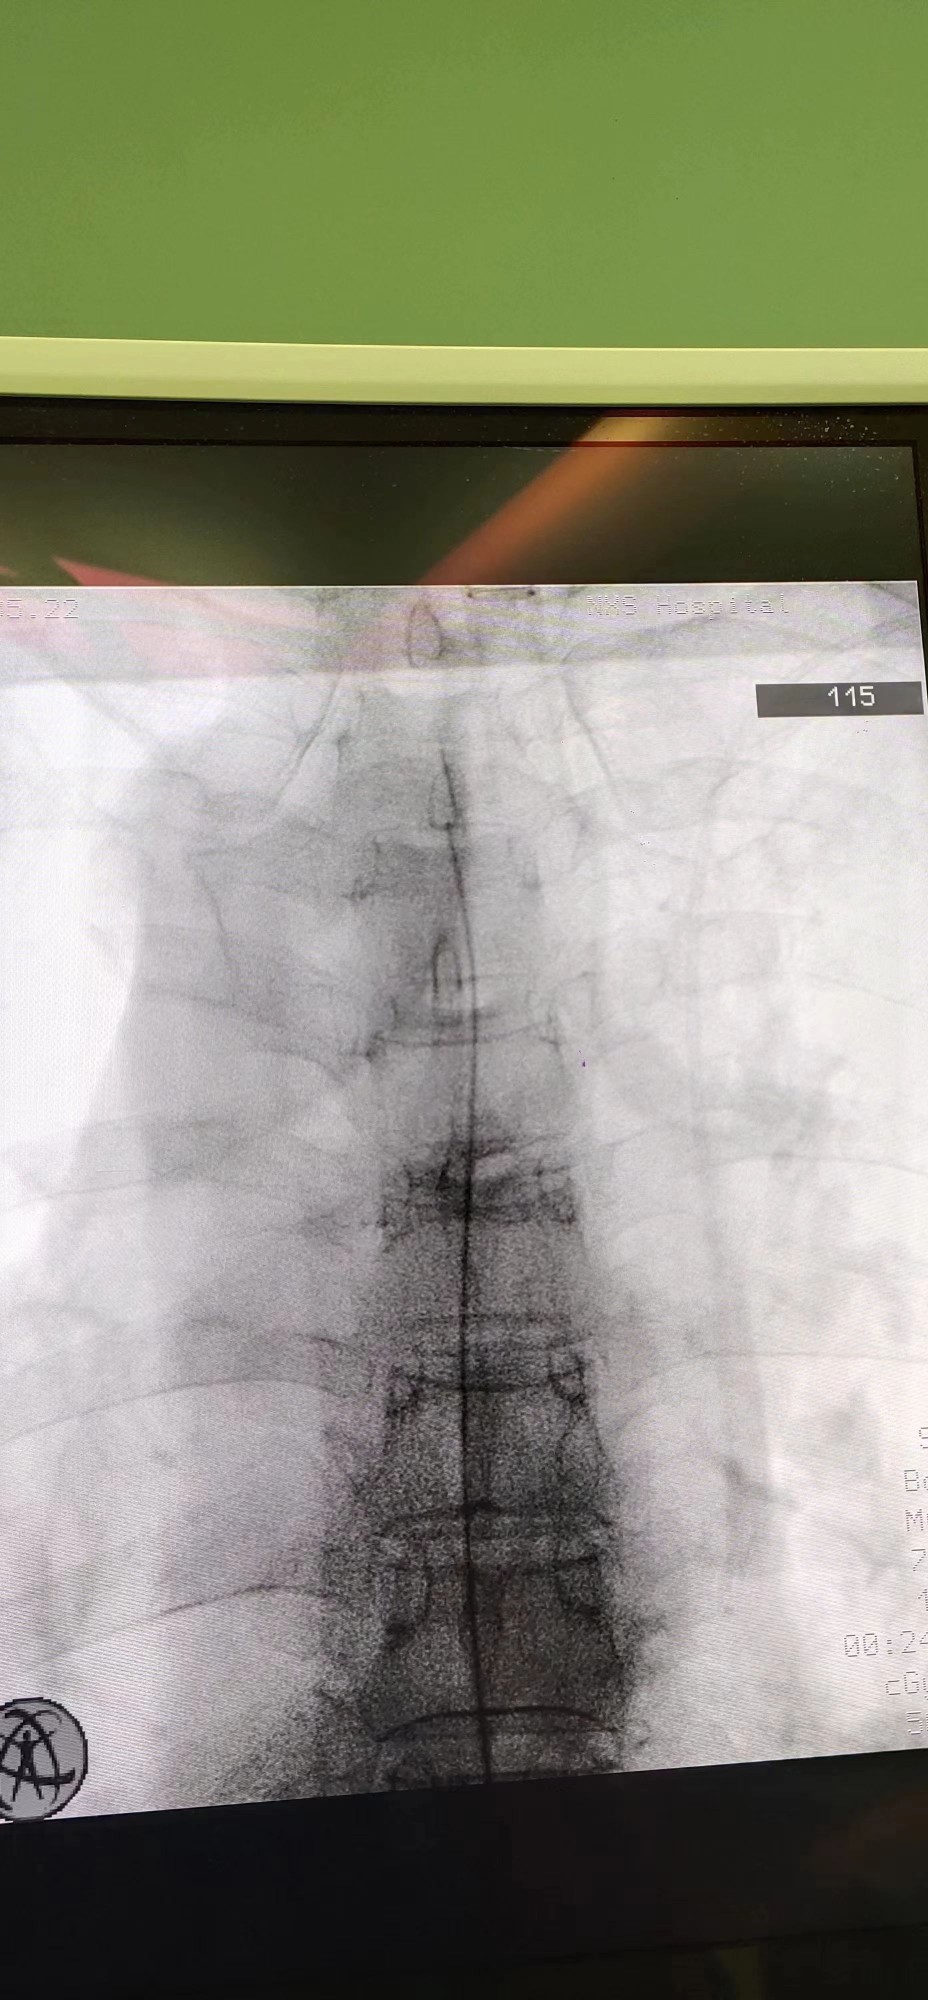

经过术前腰穿测试和充足的准备后,田文海主任团队为该患者顺利进行了全植入式鞘内药物输注系统术,患者由原来的口服盐酸羟考酮缓释片180mg/24小时,转变成每日鞘内输注0.15mg的剂量,疼痛控制效果跟口服药物相比,有了明显的提高。植入鞘内泵后,患者左侧额颞面部疼痛得到有效控制,VAS评分稳定到0~2分,日常生活质量得到极大的改善,患者再也不会因为疼痛难忍而睡不着觉了。

田文海介绍,对于难治性疼痛而言,鞘内药物灌注疗法是目前的趋势,这种疗法通过体内植入一个储存药物的泵,将镇痛药(盐酸、吗啡)直接输注到人体蛛网膜下腔的脑脊液中,使脊髓灰质相应的靶点与阿片类受体结合,阻断疼痛信号上传到大脑皮质,从而达到更快速、有效、持续性的止痛效果。相对于全身使用阿片类药物,鞘内给药更为安全,并发症和死亡率更低,所需剂量仅仅是口服药的1/300、静脉注射的1/100,极大地减轻了全身性过量药物给人体所造成的副作用。该项技术的临床应用给所有的难治性疼痛患者包括癌性疼痛,带来了远离疼痛、获得高质量生活的希望。